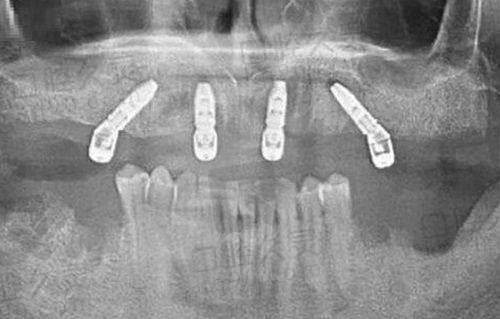

治疗方案:徐宝华医生设计隐适美全周期矫正,拔除4颗智齿,利用骨钉辅助内收前牙。

矫正成效:14个月完成矫正,前牙内收3mm,侧貌从凸面型变为直面型,患者称“同事都没发现我戴了牙套,拍照终于敢露齿笑了!”